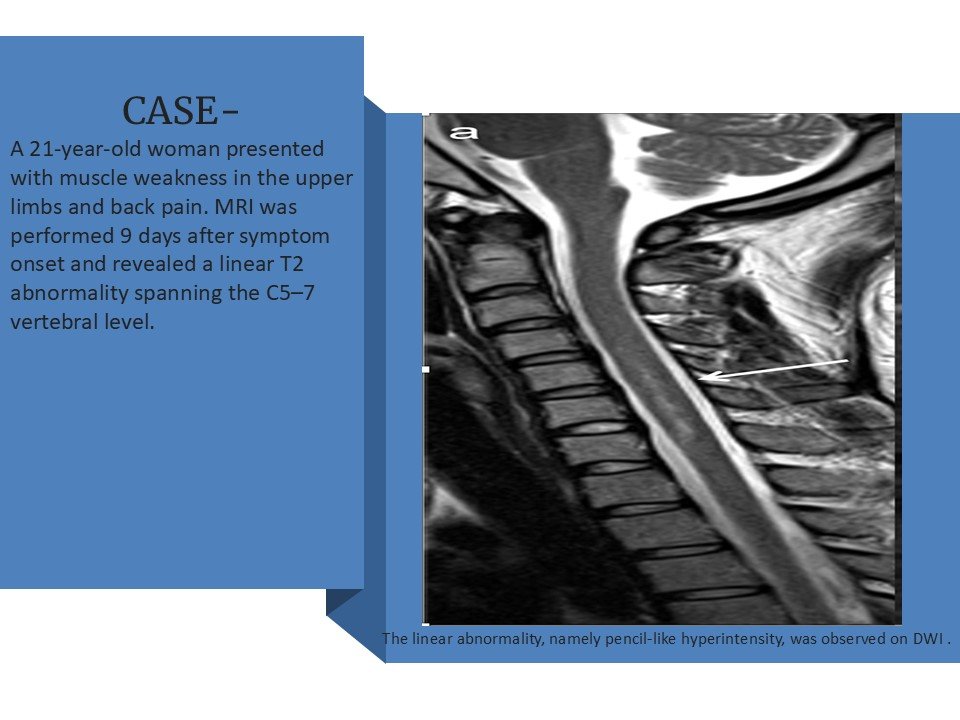

CASE-

A 64-year-old man developed neck pain after falling off a truck one week ago. T1- and T2-weighted sagittal MR images (1 and 2) are provided. What are the findings? What is your diagnosis?

• Pencil-like T2 hyperintensity.

• Anterior spinal artery territory involved.

• Restricted diffusion on DWI.

• Acute onset clinically.

At the C5/6 intervertebral level (arrows, a and b), mild T2 hyperintensities around the anterior horns were observed on the axial plane.

(c) The hyperintensities became a pair of apparent hyperintense lesions on DWI.

(d) Image corresponding to owl’s eyes sign. The lesions on the axial DWI were hypointense on ADC maps .

(e). She was diagnosed with spinal cord infarction. ADC, apparent diffusion coefficient; DWI, diffusion-weighted imaging; MRI, magnetic resonance imaging.